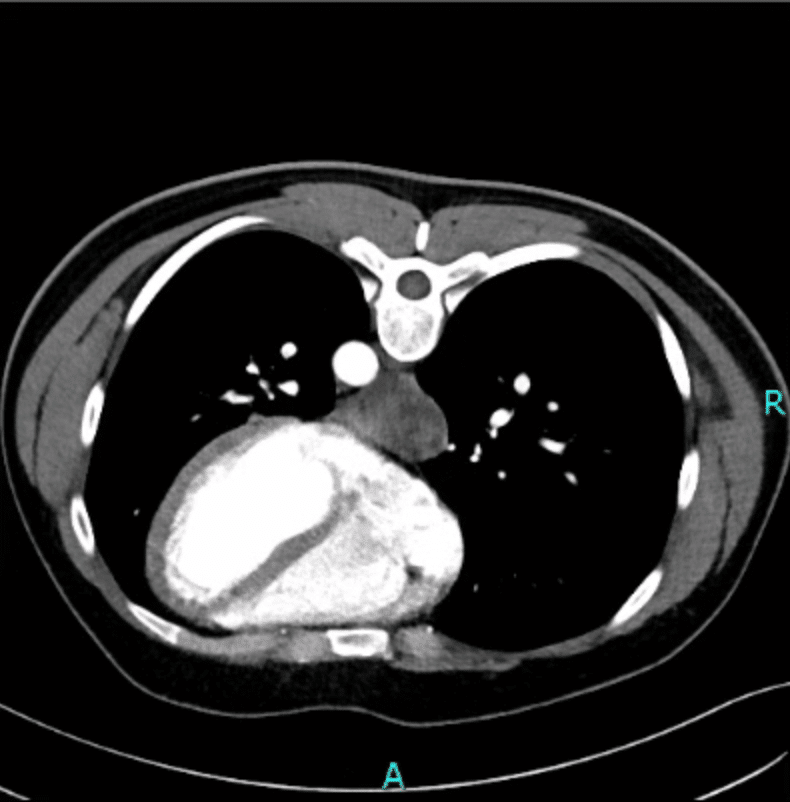

27-jähriger Patient mit akut einsetzenden, stärksten epigastrischen Schmerzen. Weitere klinische Beschwerden wurden negiert. Vorerkrankungen waren nicht bekannt. Sonographisch ergab sich ein Normalbefund. In einer CT-Angiographie stellte sich der Verdacht eines Hämatoms der distalen Ösophaguswand. In der Gastroskopie sahen wir eine Impression des distalen Ösophagus. Die Endosonographie stellte eine gemischt-echogene intramurale Raumforderung dar, sodass wir von einer spontanen Einblutung des distalen Ösophagus ausgingen. Es erfolgte eine analgetische Therapie und anschließende Verlaufskontrolle nach 2 Wochen. Klinisch wurden lediglich persistierende, leichte Schmerzen beim Schluckakt angegeben. In der Gastroskopie bestätigte sich ein spontan regredienter Befund.